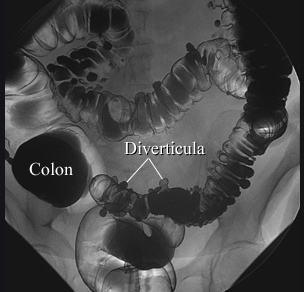

How can we view hollow viscera on abdominal x-ray?

How can we view the large intestine clearer on an AXR?

Contrast Enema